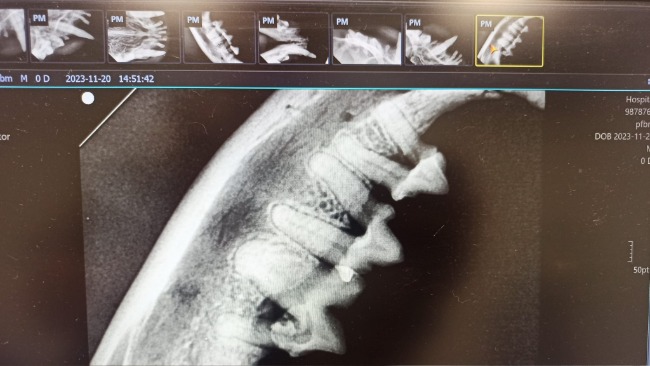

Uszko wymagał pilnej interwencji chirurgicznej, wyłamał się mu kieł, a jak się okazało prawie wszystkie zęby musiały być usunięte.

Zleciliśmy badania krwi - profil rozszerzony oraz potrzebne projekcje RTG.